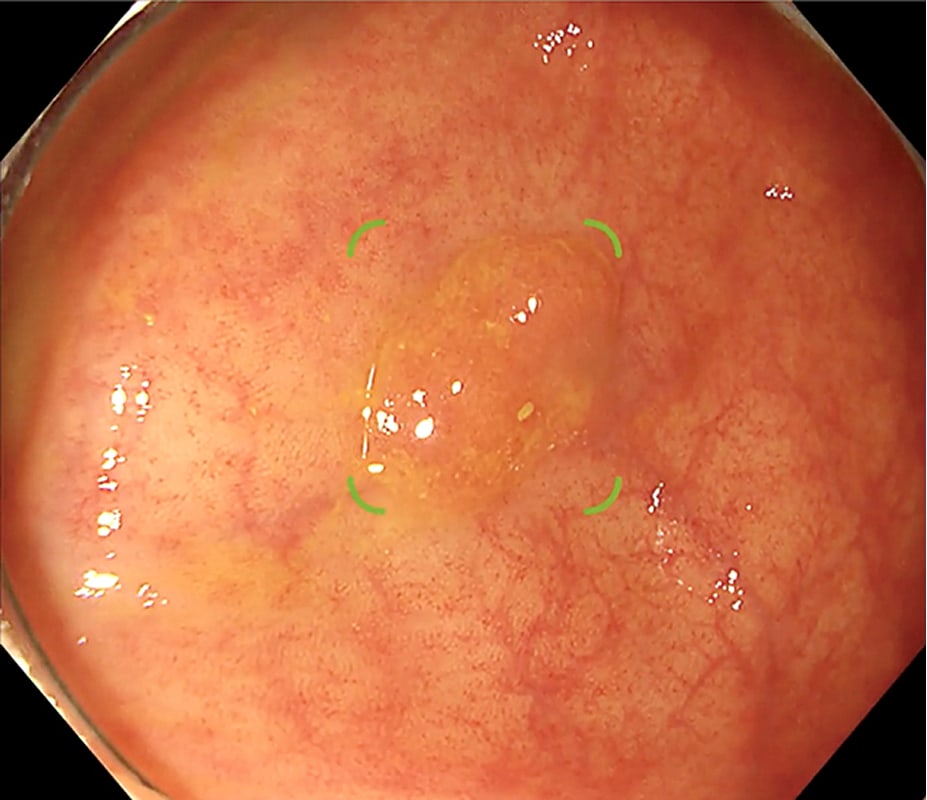

大腸ポリープ候補*を検出し、

大腸内視鏡検査を支援する

大腸内視鏡検査中に通常白色光モードにおいて入力された大腸内視鏡画像情報から、大腸ポリープ候補を検出することが出来ます。検出した場合には、メイン画像の四隅を囲むアラート枠を表示した後、ポリープ候補領域の四隅を囲む矩形を表示します。

* 隆起型及び表面型(表面隆起型)